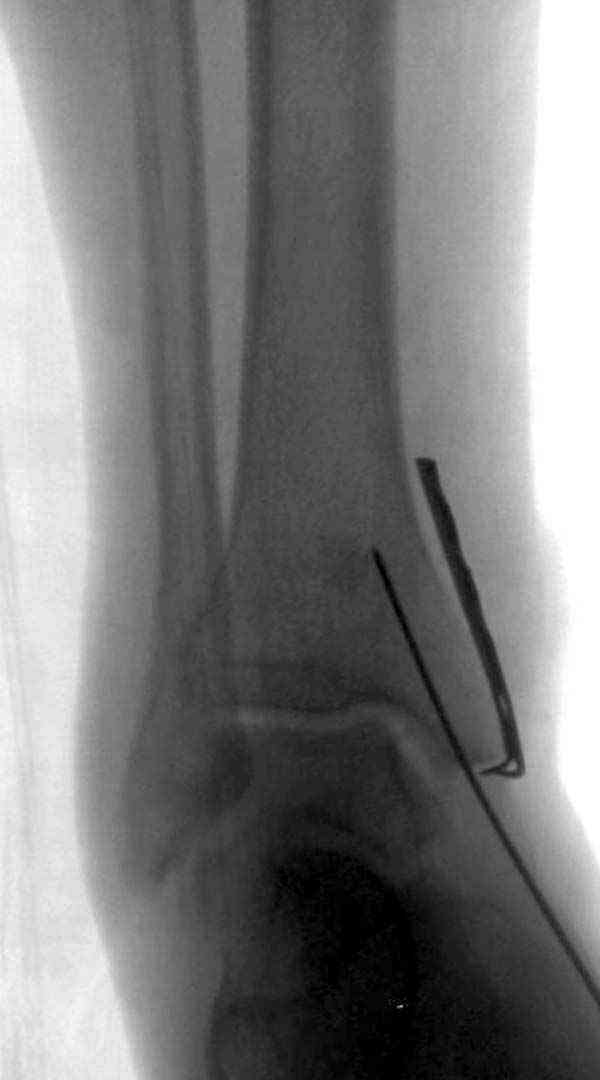

Достаточно быстрое восстановление функции.В октябре 2009г-почувствовала боль,в области рубца над гайкой открылся свищ.На Р-граммах-консолидация переломов и смещение гайки по стяжке.10.11.2009г-конструкции удалены,санация,заживление ран.В настоящее время пациентку ничего не беспокоит.На операции-раскручивание гайки-болталась на конце стяжки.Вопросы:какой механизм раскручивания и что я неправильно сделал?Свои версии:1)в области синдесмоза успела образоваться рубцовая ткань,которая при движении в суставе"пружинила",поскольку голеностопный сустав является спиральным, то и биомеханика подобна кривошипному механизму.2)Реконструктивная пластина не "реконструировалась" по форме лодыжки.Наложил,как есть.То есть подпружинивала сама пластина.Ну,это мои догадки.Что нужно,чтобы избегать впредь таких,пусть и не "страшных"осложнений:Рассверливать через лодыжку область синдесмоза?Ставить шайбу-гровер?Тщательно моделировать пластину?Прилагаю сравнительные снимки-сразу после операции и перед удалением конструкции.

Раз ,есть желание посмотреть другую проекцию выкладываю-ну лучшего качества нет...